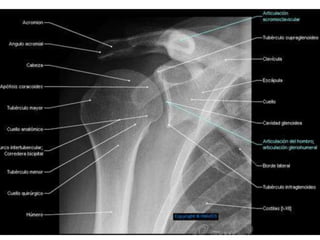

Fractura de clavícula:

Rx. Simple de hombro en proyección antero-posterior que incluya la

articulación esterno-clavicular hasta la porción lateral del húmero.

Agregar radiografía de tórax si se sospecha neumo o hemotórax.

TAC cuando se sospecha de lesión intra-articular o cuando la fractura se

encuentra en los extremos del hueso.